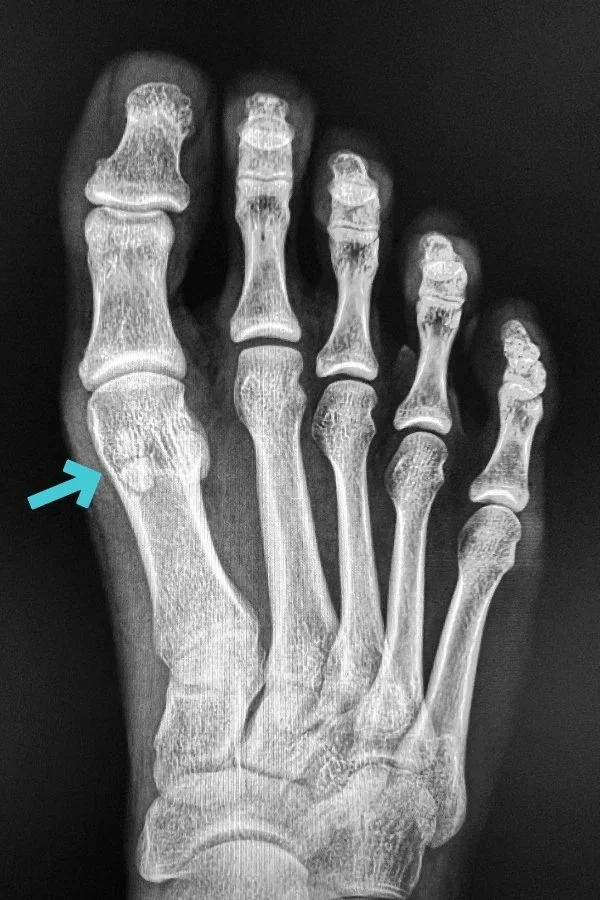

Sesamoid Bone Big Toe Pain. sesamoiditis is pain around the two small bones (the sesamoid bones) below the metatarsal head where it adjoins the big. you may experience aching increasing to intense pain located beneath your big toe and in the ball of your foot. An acute fracture is caused by trauma—a direct blow or impact to the bone. sesamoiditis of the foot is a fairly common condition that causes forefoot pain. It is an overuse injury causing gradual onset pain in the forefoot. You may also have a “pop” sensation in. the painful sesamoid can be a chronic and disabling problem and isolating the cause can be far from straightforward. sesamoiditis refers to irritation and inflammation of the tendons surrounding the sesamoid bones. A fracture (break) in a sesamoid bone can be either acute or chronic. sesamoiditis and gout can affect the bones, joints, tendons, and other tissues of the big toe and foot. The most common is arthritis. during an examination physiotherapist will look for tenderness at the site of sesamoid bones. Pain when the great toe is forcefully pulled upwards (dorsiflexion of the great toe) sesamoiditis affects the small sesamoid bones under the base of the big toe. the pain of sesamoiditis is felt beneath the base of the big toe (the first metatarsal joint).

you may experience aching increasing to intense pain located beneath your big toe and in the ball of your foot. Pain is felt under the big toe joint. most patients with a sesamoid fracture describe a deep, achy, or sharp pain in the ball of the foot behind the big toe with every step taken. Pain with pressure applied directly to the sesamoid bones. Sesamoid problems are usually detectable by a careful history and examination. sesamoiditis is pain around the two small bones (the sesamoid bones) below the metatarsal head where it adjoins the big. An acute fracture is caused by trauma—a direct blow or impact to the bone. To do this physiotherapist may. sesamoiditis pain is often associated with a dull, longstanding pain beneath the big toe joint. examine your foot and big toe, looking for tenderness that is localized to (only felt in the area of) the sesamoid bones.

Sesamoid Bone Big Toe Pain The pain comes and goes, usually. the painful sesamoid can be a chronic and disabling problem and isolating the cause can be far from straightforward. sesamoiditis, also known as inflammation of the sesamoid bone of the big toe, is a common cause of big toe pain in. sesamoiditis refers to irritation and inflammation of the tendons surrounding the sesamoid bones. It may even hurt to move that toe. The pain comes and goes, usually. The most common symptoms include: sesamoiditis can make it difficult to straighten or bend your big toe. most patients with a sesamoid fracture describe a deep, achy, or sharp pain in the ball of the foot behind the big toe with every step taken. pain from a sesamoid injury is focused under the big toe on the ball of the foot. Pain with pressure applied directly to the sesamoid bones. An acute fracture is caused by trauma—a direct blow or impact to the bone. It is an overuse injury causing gradual onset pain in the forefoot. during an examination physiotherapist will look for tenderness at the site of sesamoid bones. Pain when the great toe is forcefully pulled upwards (dorsiflexion of the great toe) the pain of sesamoiditis is felt beneath the base of the big toe (the first metatarsal joint).